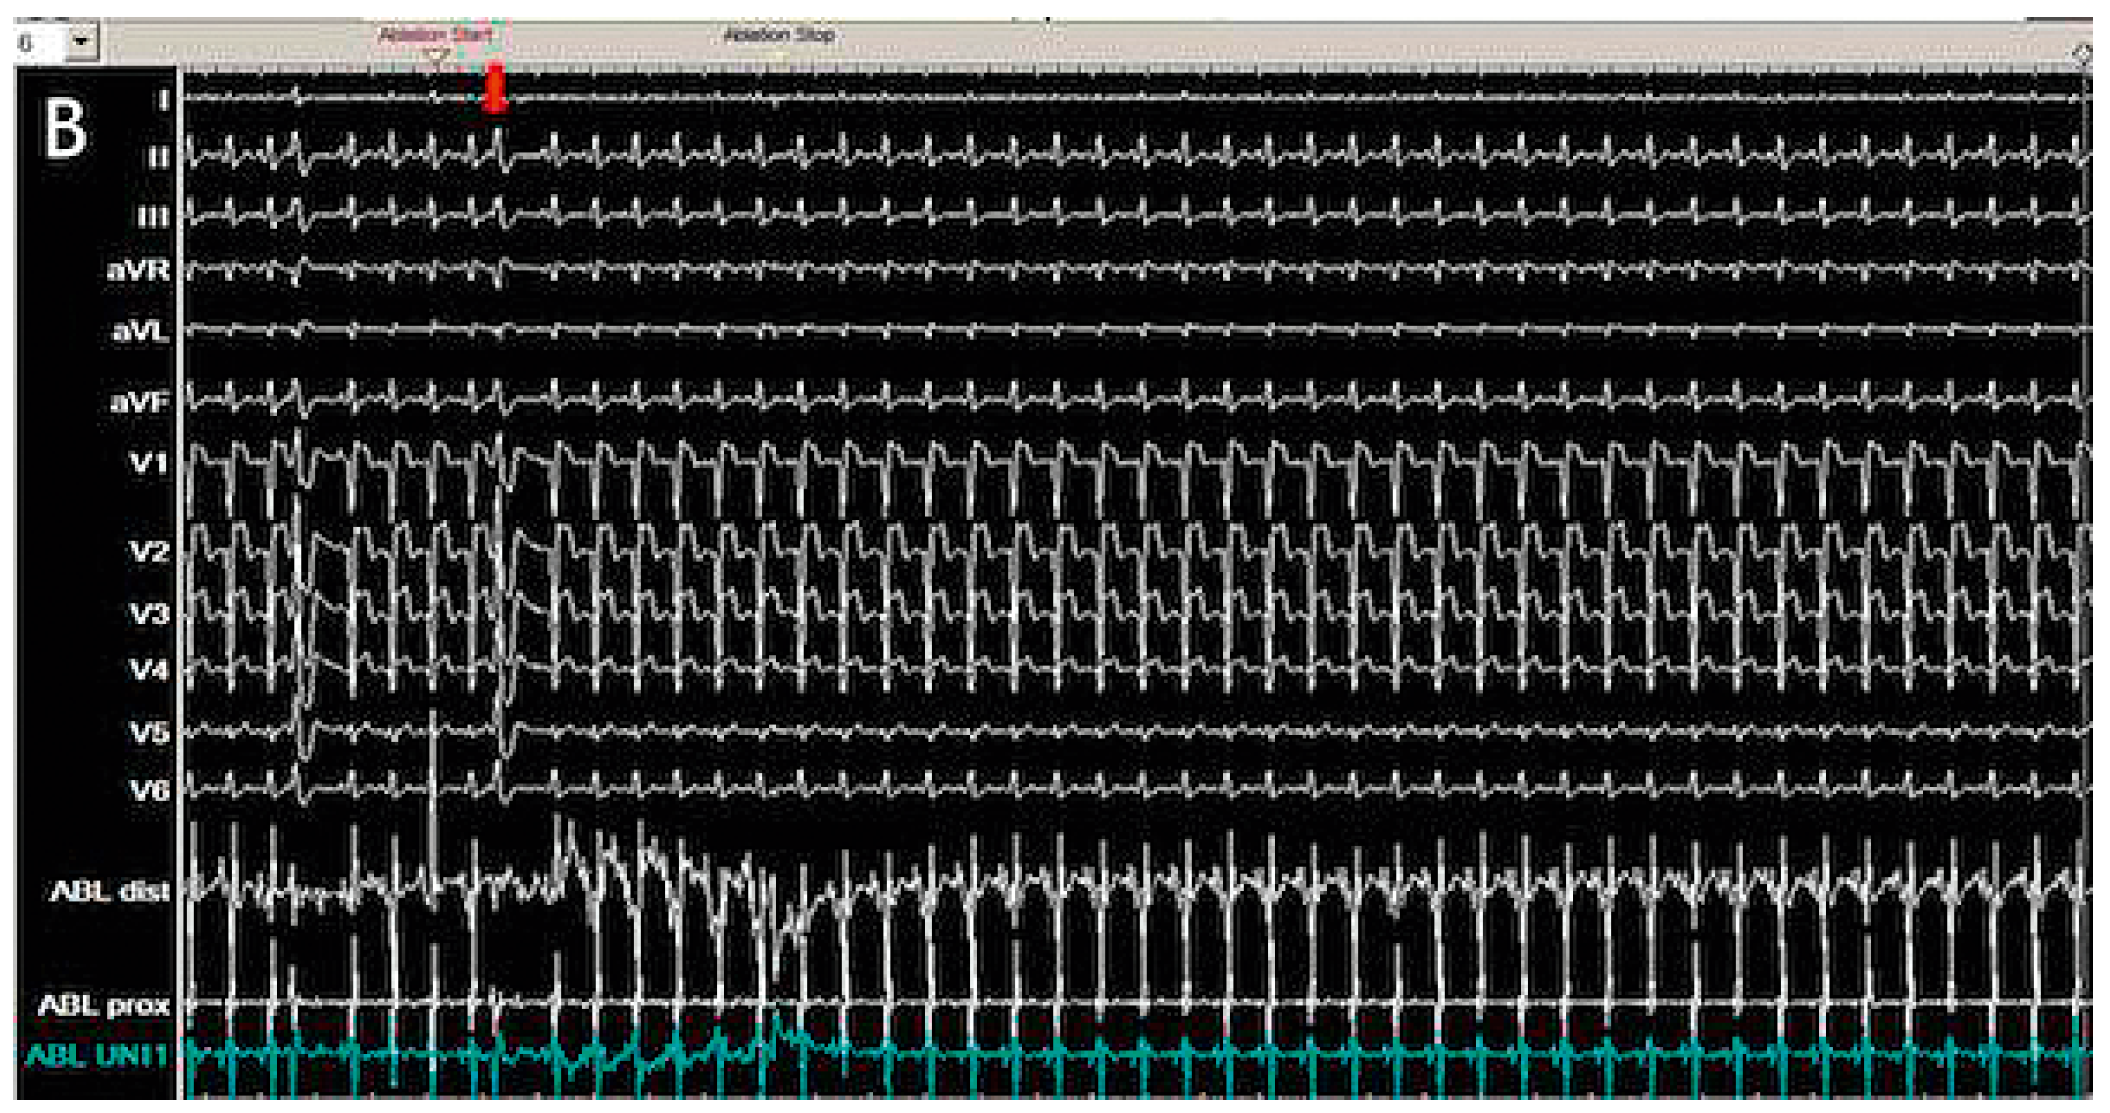

O14—Cardiac metastasis of a lung adenocarcinoma manifesting as an electrical storm

A 66-year old female was hospitalized in our Cardiovascular Department for a first episode of syncope. Clinical history revealed smoking and hypercholesterolemia. The baseline ECG showed repetitive non-sustained ventricular tachycardia (VT) of rather narrow QRS duration originating from the infero-basal interventricular septum (IVS) or from the right moderator band (Figure 1). A coronary angiography revealed a 50–70% stenosis of the left main coronary artery treated with the implantation of an active stent.The echocardiography was non-contributive, but the cardiac MRI revealed a localized thickening of the inferior IVS (Figure 2A) with hyperintense inhomogeneous appearance on T2-weighted images (Figure 2B) confirmed by elevated T2 values (60 ms, normal values <55 ms; Figure 2D) and T1 values (1184 ms, normal values <1050 ms; Figure 2C); the high signal intensity on late gadolinium enhancement (LGE, Figure 2E-2F) was indicative of a large interstitial space secondary to edema (high T2 and T1 values) and hypervascularization. The following differential diagnoses were considered: cardiac sarcoidosis, metastatic tumor or infectious disease. Endomyocardial biopsy samples taken from the IVS did not show any malignant cells or granuloma. An electrophysiological study did not show any susceptibility to sustained ventricular arrhythmias. The unexplained 8-Kg weight lost over the past year in a smoker patient raised the suspicion of malignancy. An 18FDG-PET scan performed after a 24-hour carbon hydrate free diet revealed a focal hypermetabolic activity within the IVS at the site of LGE (Figure 2G). Interestingly, a hypermetabolic nodule in the upper lobe of the right lung (Figure 2H) together with active paratracheal lymph nodes were suggestive of a metastatic lung cancer, that was confirmed by cytoponction of paratracheal lymph nodes (non-small cell lung cancer: NSCLC). The patient started a combination chemotherapy with carboplatin and pemetrexed and now is followed by the oncologists and the cardiologists.

Conclusions: this clinical case represents an unusual manifestation of lung cancer (NSCLC) with cardiac metastasis presenting with repetitive non-sustained ventricular tachycardia. In this patient, cardiac MRI allowed to detect the cardiac metastasis and was useful to guide the endomyocardial biopsy and the elettrophysiological study.

![]() |

| Figure 1. ECG. |